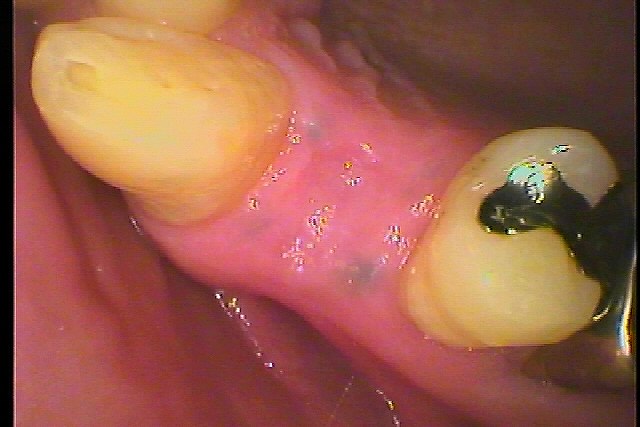

取れた歯を見るとかなり虫歯になっていました

黒く虫歯になっています

このように歯茎が治ってきました